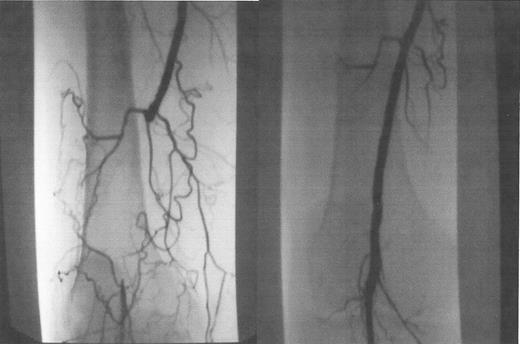

Occluded popliteal artery, before (A) and after (B) laser-assisted balloon angioplasty.

Laser-assisted balloon angioplasty is an endovascular technique that allows recanalization of long segment arterial occlusions that are too long to be successfully crossed with a guidewire and conventional techniques alone. Most short segment arterial occlusions can be crossed using standard guidewires with hydrophilic coatings that enable the wire to be “slipped” through an obstructed area. In some long segment lesions, however, this is not possible. The excimer laser device (Spectranetics, Colorado Springs, CO), on the other hand, is advanced in small increments along with the guidewire, while the laser energy recanalizes the occluded arterial segment. Once the diseased segment is crossed, a standard guidewire is placed through the area and it is treated with balloon angioplasty as with other arterial stenotic lesions (Figure 6 ). These devices come in a range of diameters (0.9–2.5 mm) and can be used for coronary and peripheral arterial lesions.